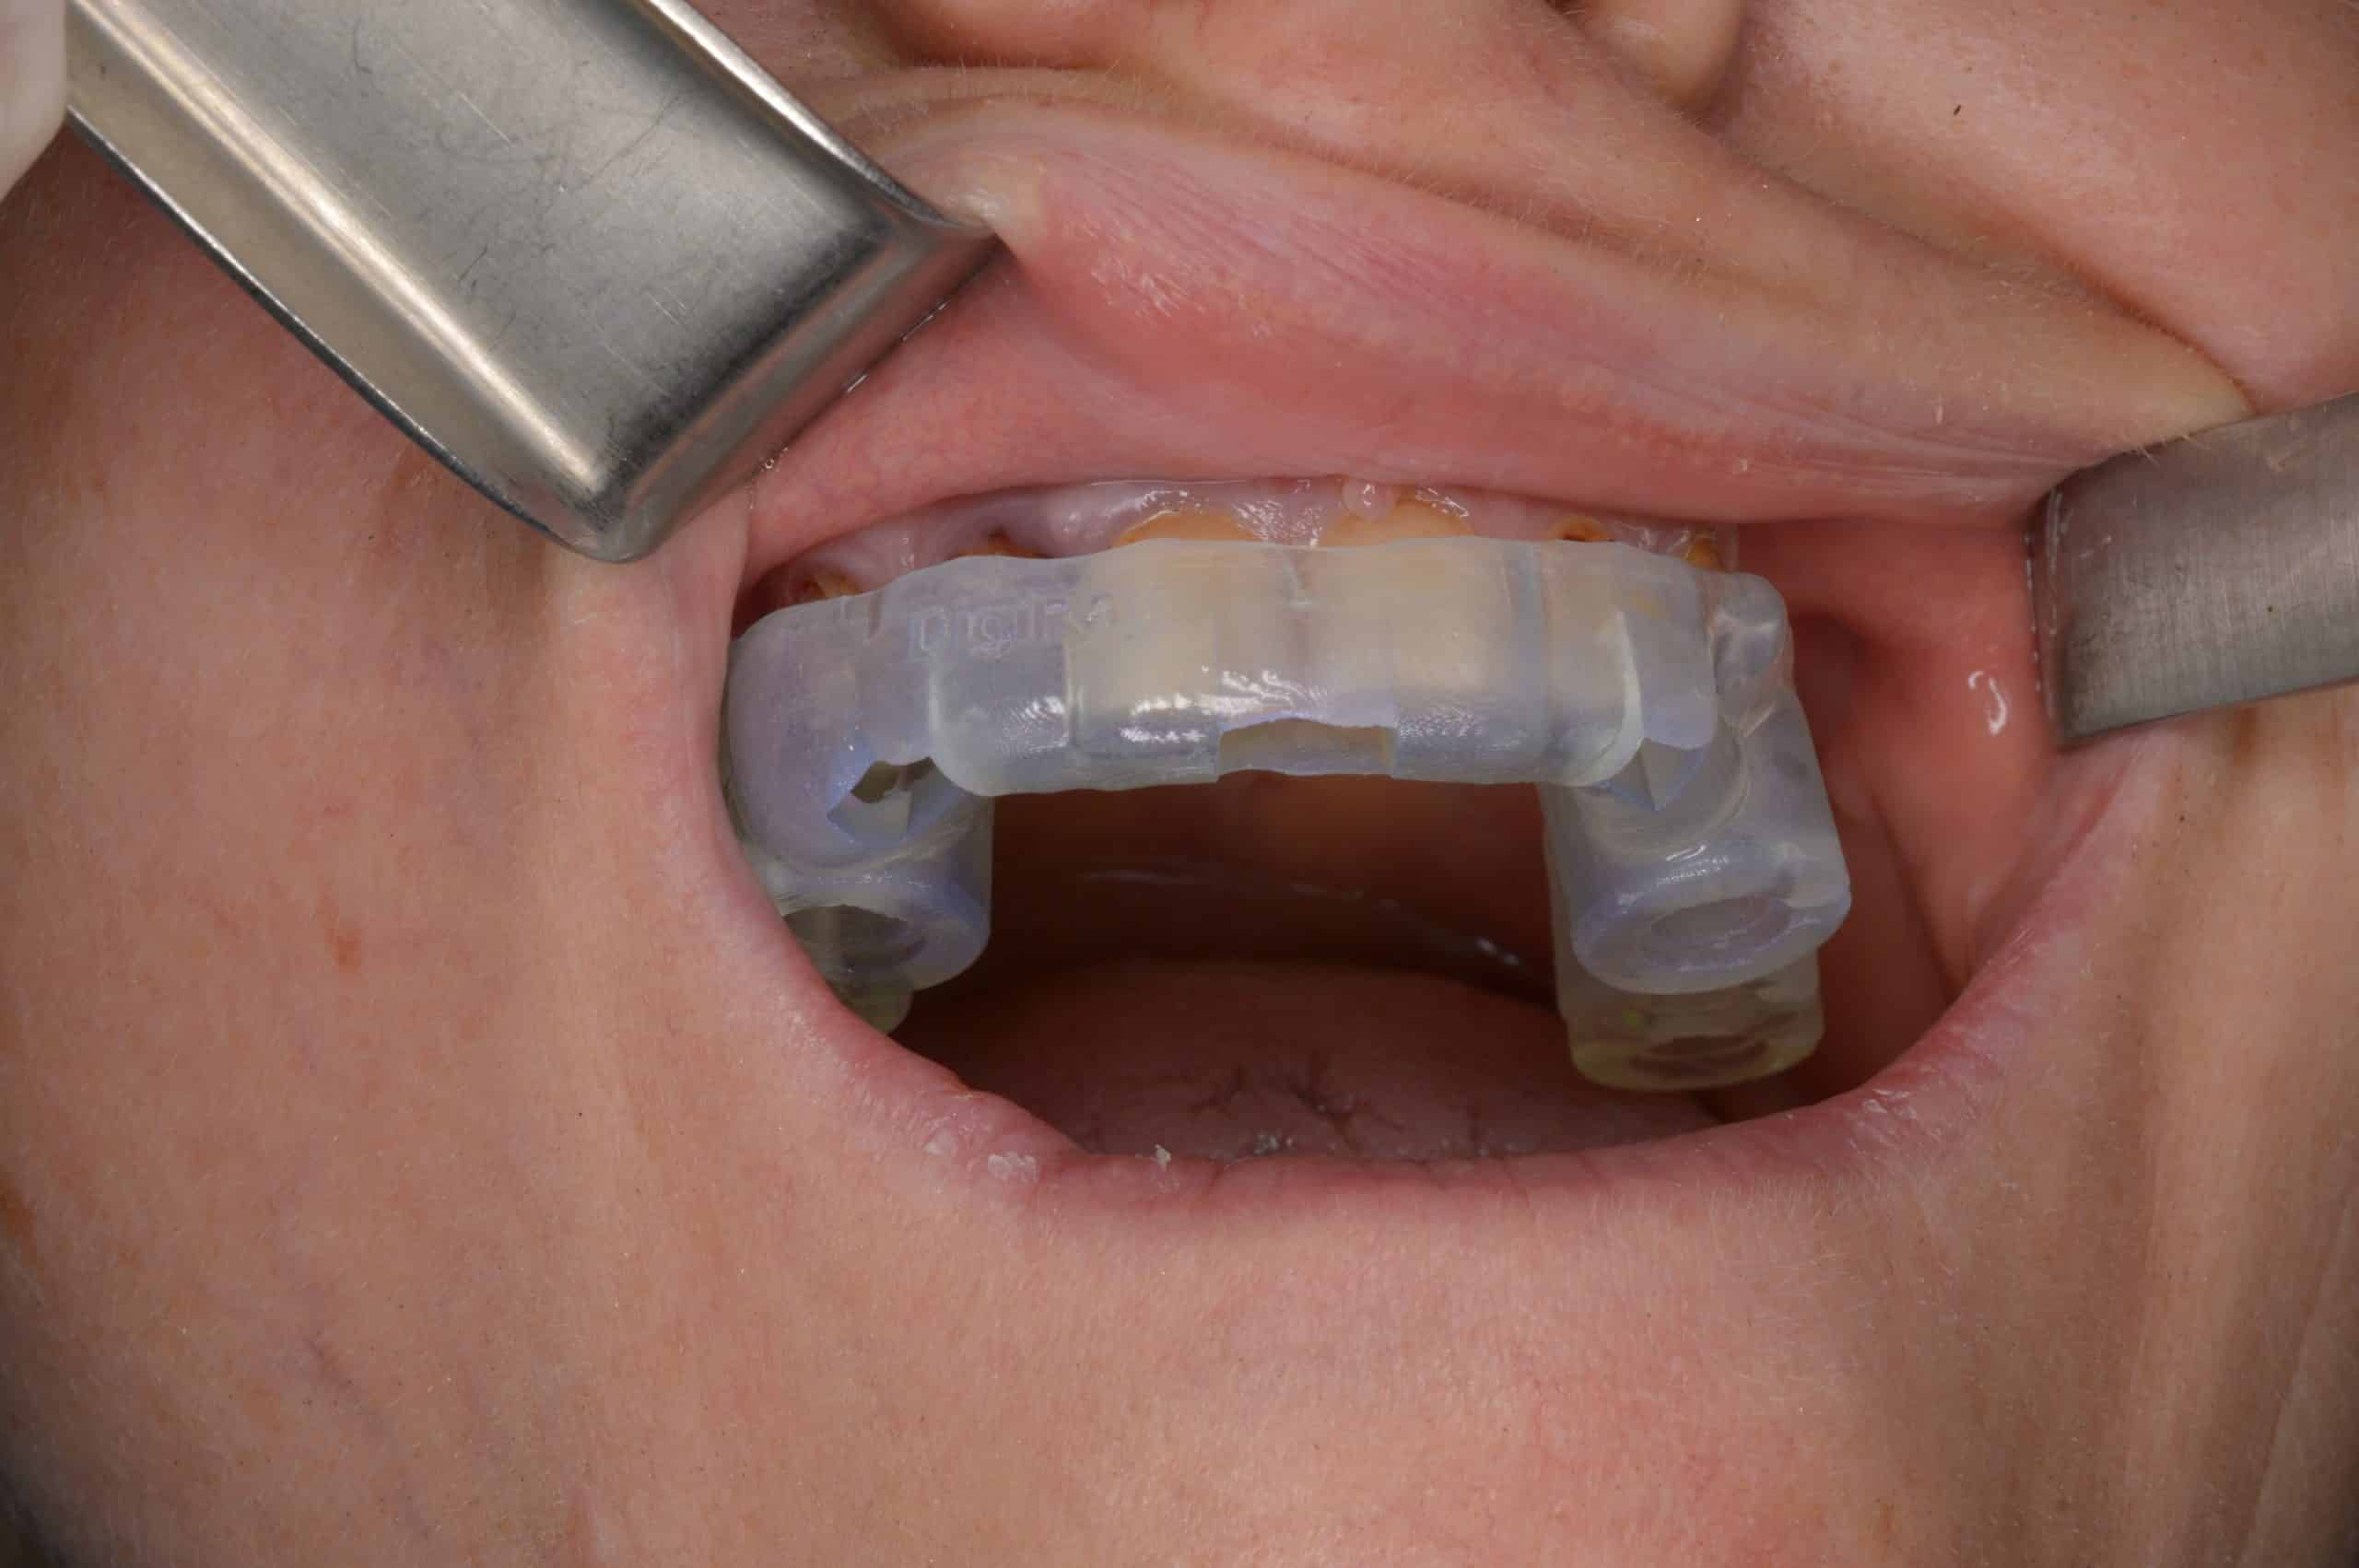

Medicul a verificat stabilitatea ghidului chirurgical pe dinți. Cu toate că extracțiile dinților 12, 13 și inserarea implantului în pozitia 12 nu au fost planificate în prealabil, ghidul chirurgical a avut stabilitate excelentă.